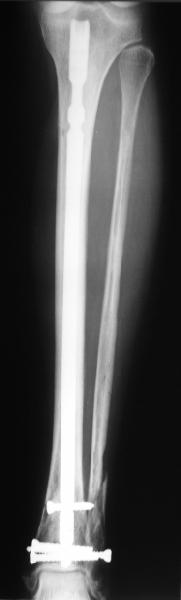

A typical case is attached, also an image with intra-op reduction obtained by a small wire distractor, in the moment of insertion a Poller wire in AP direction. Fixation by a SIGN nail. Despite the fibula was not fixed healing was obtained with the unchanged alignment.

Very interesting application, but is the final position in a little distal varus with some fibula

distraction? Would that have been eliminated by fibula plating?

TDVC> little distal varus with some fibula distraction?

At least both the ankle mortise and tibial alignment look acceptable, don't they?

I am just trying to illustrate that prevention of 1)tibial valgus and 2)loss of reduction can be provided without fibular plating. Small changes of conventional nailing techniques allow to maintain reduction of the tibia reliably without adjunctive fibular stabilization.